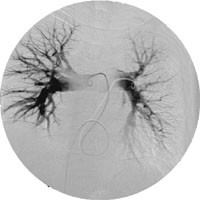

Spiral-CT av thorax viste massiv lungeembolisme med ein stor, sentral embolus i høgre grein av arteria pulmonalis og fleire perifere embolusar i begge lunger (fig 1). Ultralydundersøking av lårvener bilateralt viste ingen teikn til venetrombose. I same seanse som den trombolytiske behandlinga vart det gjort cavagrafi, som ikkje viste teikn til trombose i bekkenvener eller v. cava, og pulmonal angiografi, som stadfesta forholda i lungekretsløpet.

Ny spiral-CT neste dag viste opne arteriar bilateralt, bortsett frå ein underlappsarterie dorsalt på høgre side, der det framleis var små trombemassar (fig 2).